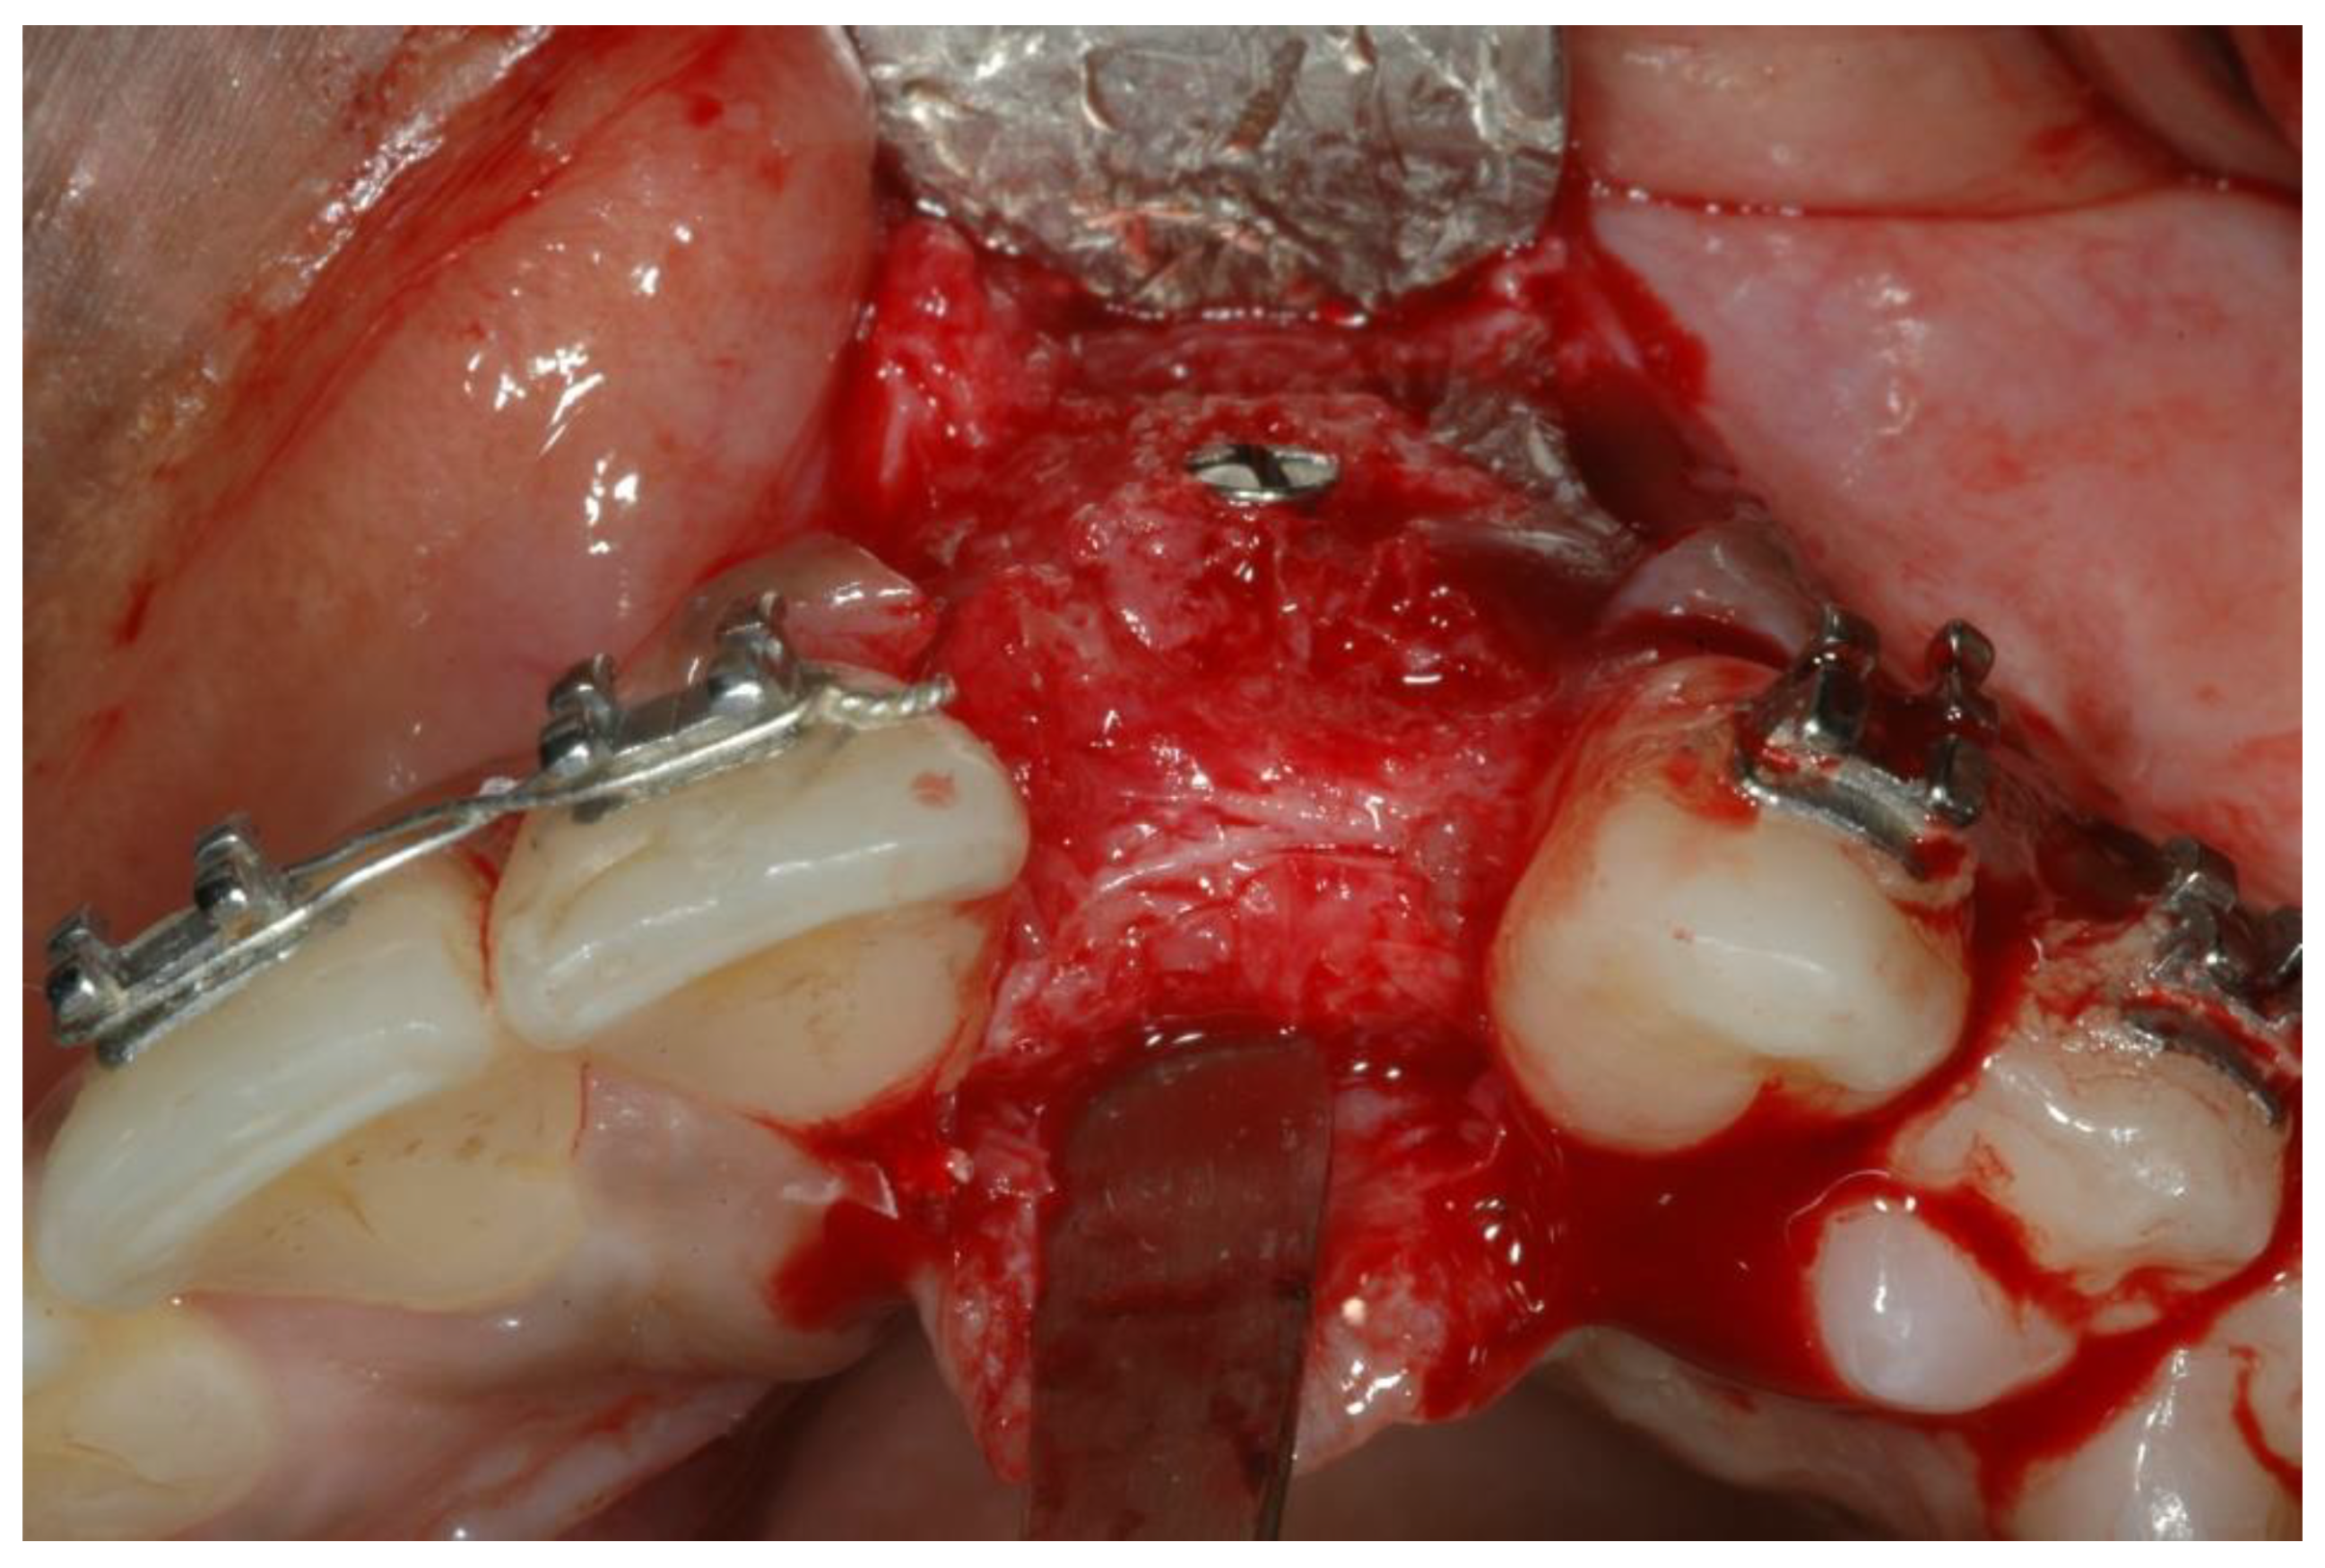

- Bone augmentations using cancellous allogeneic bone-blocks.

- Six months later, implant insertion followed immediately by a temporary restoration placement.